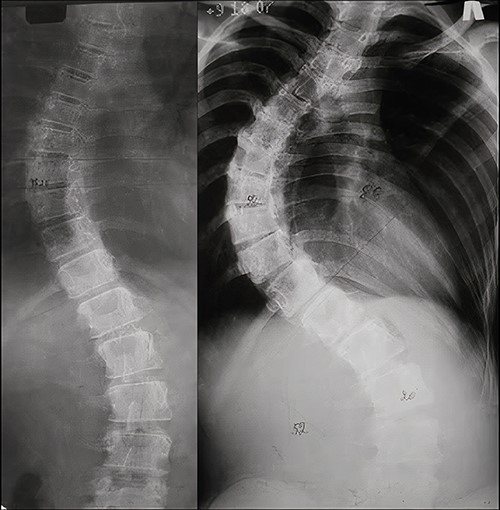

The patient was referred to our center in 2006 at the age of 11 with a right-sided thoracic curve and a left-sided lumbar curve. The patient’s sitting height was 71 cm and weight was 45 kg. There were no neurological symptoms. Diagnosis at presentation: adolescent thoracic idiopathic scoliosis with deformity angle of 43° (Fig. 2a). The patient’s parents refused surgical treatment in favor of bracing. The treatment was ineffective and deformity progressed within a year. At a follow-up examination at the age of 12, the main thoracic curve deformity angle progressed to 88°, with a lumbar curve of 52°. At that time, the patient was a Risser 2 (Fig. 2b).

AP X-rays of the patient’s spine. (a) At 11 years old in standing position. A 43° main thoracic curve is visualized. (b) At a 1-year follow-up (12 years old, standing position). A main thoracic curve of 88° and a lumbar curve of 52° are visualized.